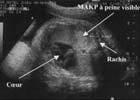

L'échographie met en évidence une masse intra-thoracique [7] :

Le doppler couleur ne retrouve pas de flux à l'intérieur de ces kystes. Il ne retrouve pas non plus de vascularisation aberrante provenant directement de l'aorte.